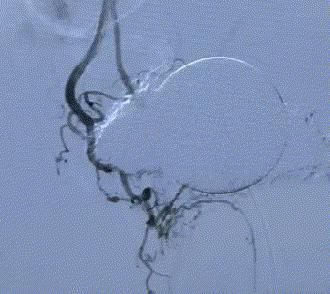

随後,李旭丹主任攜手胡志華主任爲患者實施介入治療,采用改良Seldinger法穿刺股動脈,在DSA引導下經動脈自然腔道,将微導管分别送達雙側髂内動脈進行造影,觀察雙側前列腺動脈分布情況,将微導管超選擇至雙側前列腺動脈,準确置入PVA栓塞材料,成功阻斷前列腺的營養供給,順利完成了治療。

△術前,可見前列腺供血豐富。